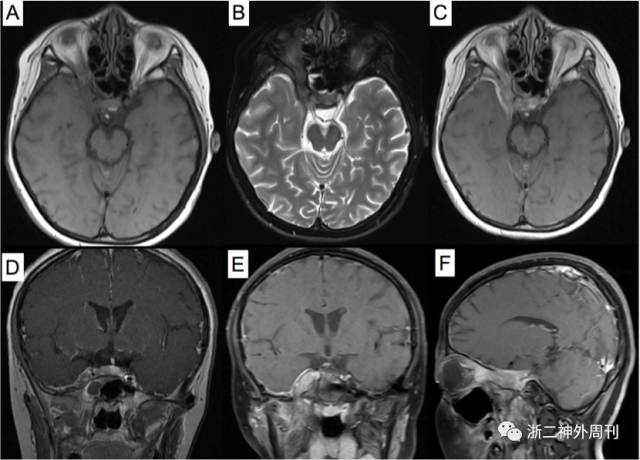

患者,女,11岁,因“头痛3月余,面部浮肿10天”入院。患者3月余前无明显诱因下出现头痛,无恶心呕吐,无畏寒发热,无四肢抽搐等。遂至我院儿科就诊,查CT及MRI示:右眶尖-海绵窦-颞下窝病变,考虑炎症性病变可能,肿瘤不能除外(图1)。今为求进一步诊治,拟以“海绵窦肿瘤”收住入院。

图1. 术前MRI检查:A)T1加权轴位;B)T2加权轴位;C)增强像轴位;D-E)增强后冠状位和F)矢状位示右眶尖-海绵窦-颞下窝病变,呈等T1、略长T2信号,增强后明显强化,邻近脑膜增厚伴强化。